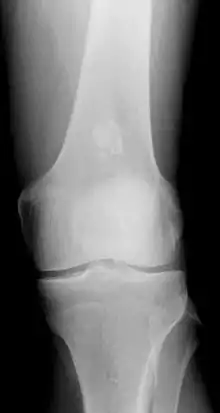

- x-ray - On plain film, an enchondroma may be found in any bone formed from cartilage. They are lytic lesions that usually contain calcified chondroid matrix (a "rings and arcs" pattern of calcification), except in the phalanges. They may be central, eccentric, expansile or nonexpansile.

Differentiating an enchondroma from a bone infarct on plain film may be difficult. Generally, an enchondroma commonly causes endosteal scalloping while an infarct will not. An infarct usually has a well-defined, sclerotic serpentine border, while an enchondroma will not. When differentiating an enchondroma from a chondrosarcoma, the radiographic image may be equivocal; however, periostitis is not usually seen with an uncomplicated enchondroma.